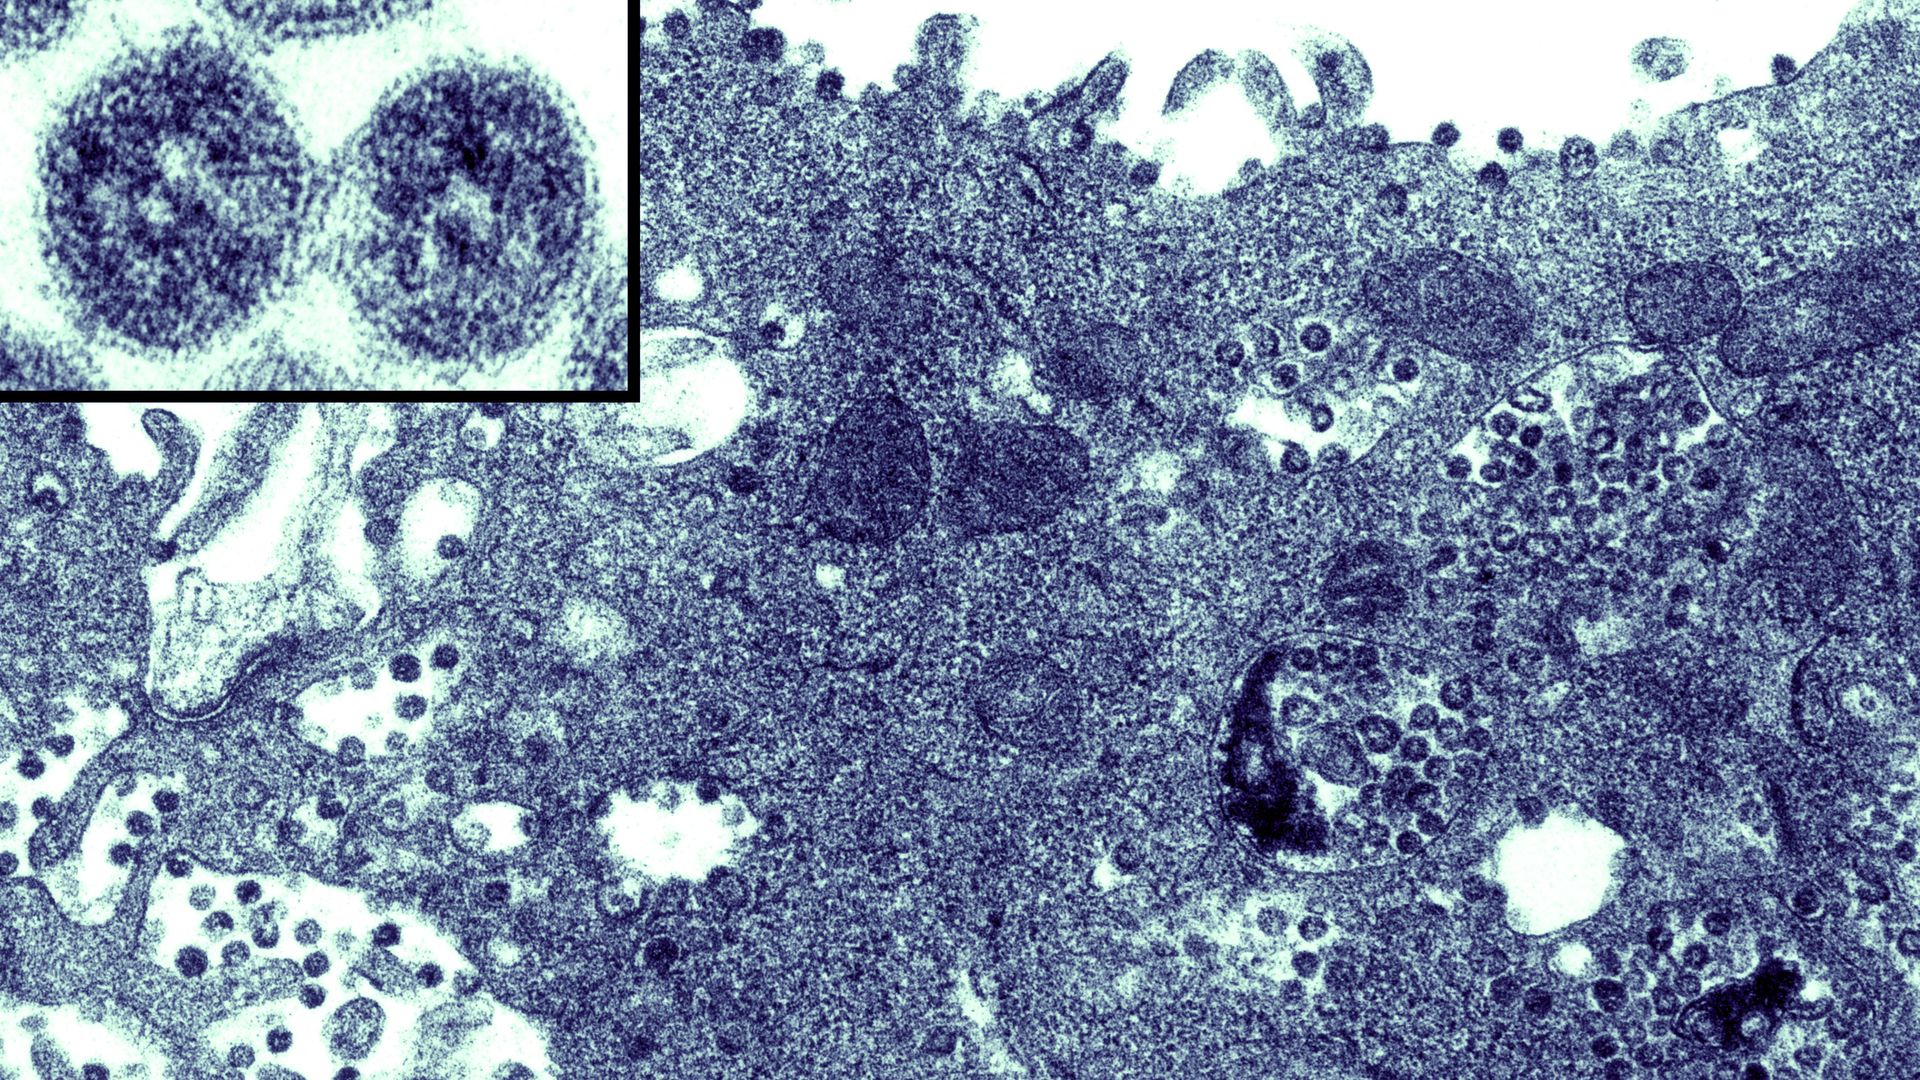

Coronavirus contained within the endoplasmatic reticulum of a vero E6 cell. Photo: BSIP/UIG Via Getty Images